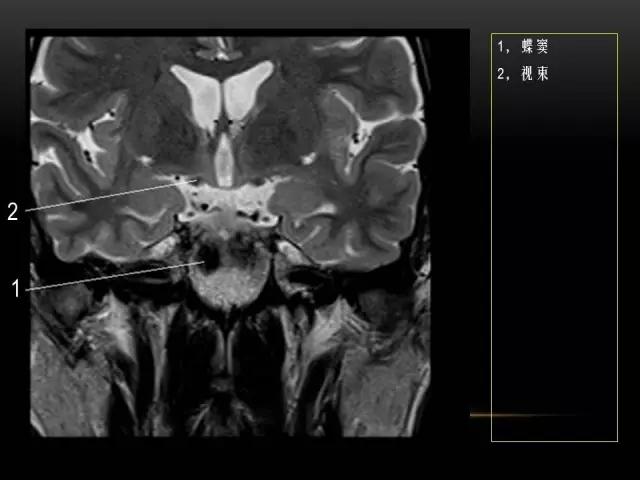

下文是在MRI下眼部及鼻窦的冠状位解剖图谱。